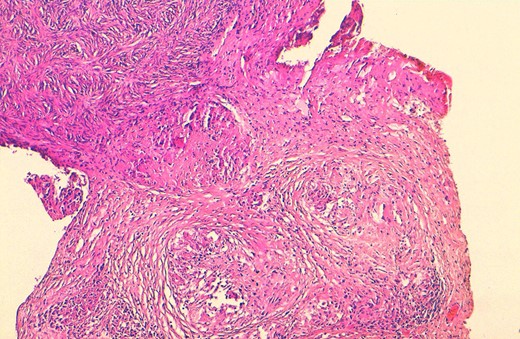

A substantial proportion of women’s specimens were addressed for histopathological analysis for malignant suspicion on clinical examination and on imaging techniques (seven cases, 53.84%). These patients presented with abnormal bleeding (especially metrorrhagia in older patients) or with mass-forming lesions on clinical examination and on imaging techniques. Diverse surgical procedures were performed on eight cases (61.53%). Most patients had multifocal FGTB (9 cases, 69.23%) with extragenital involvement especially peritoneal or lymph node locations (five and two cases respectively). The most involved genital organs (whether solely or with other organs) were fallopian tubes (63.84%), ovaries (46.15%), endometrium (38.46%) and the cervix (23.07%). The patient No-8 had a concomitant cervical adenocarcinoma. The macroscopic aspects of all resected specimens did not show the classic cheese-like appearance of the caseous necrosis (Fig. 1), rather they show morphologic abnormalities (distended fallopian tubes, hard endometrium), haemorrhage, cystic changes or ischaemic necrosis. The histopathological analysis showed granulomatous lesions associated with variable amount of caseous necrosis (Figs 2 and 3). All patients were HIV-negative, they received the standard antibiotic therapy (combination of rifampicin, isoniazid, ethambutol and pyrazinamide).

Macroscopic view: an illustrative case of lymph node tuberculosis with cheese-like appearance of the caseous necrosis (arrow).

Histological view showing ovarian parenchyma with granulomatous lesions and caseous necrosis (H&E × 100).